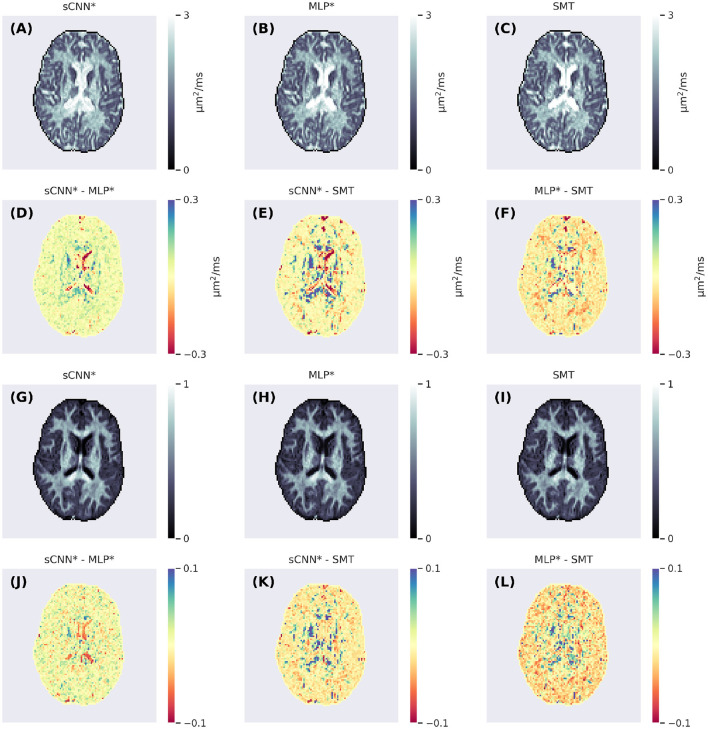

Diffusion magnetic resonance imaging is sensitive to the microstructural properties of brain tissue. However, estimating clinically and scientifically relevant microstructural properties from the measured signals remains a highly challenging inverse problem that machine learning may help solve. This study investigated if recently developed rotationally invariant spherical convolutional neural networks can improve microstructural parameter estimation. We trained a spherical convolutional neural network to predict the ground-truth parameter values from efficiently simulated noisy data and applied the trained network to imaging data acquired in a clinical setting to generate microstructural parameter maps. Our network performed better than the spherical mean technique and multi-layer perceptron, achieving higher prediction accuracy than the spherical mean technique with less rotational variance than the multi-layer perceptron. Although we focused on a constrained two-compartment model of neuronal tissue, the network and training pipeline are generalizable and can be used to estimate the parameters of any Gaussian compartment model. To highlight this, we also trained the network to predict the parameters of a three-compartment model that enables the estimation of apparent neural soma density using tensor-valued diffusion encoding.